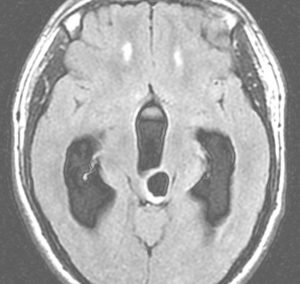

左は正常な子どもの脳室です。右は第4脳室腫瘍のために軽度の水頭症になった子どもの脳室です。髄液が溜まって側脳室が拡大していますが,このくらいだと緊急に手術をする必要はありません。